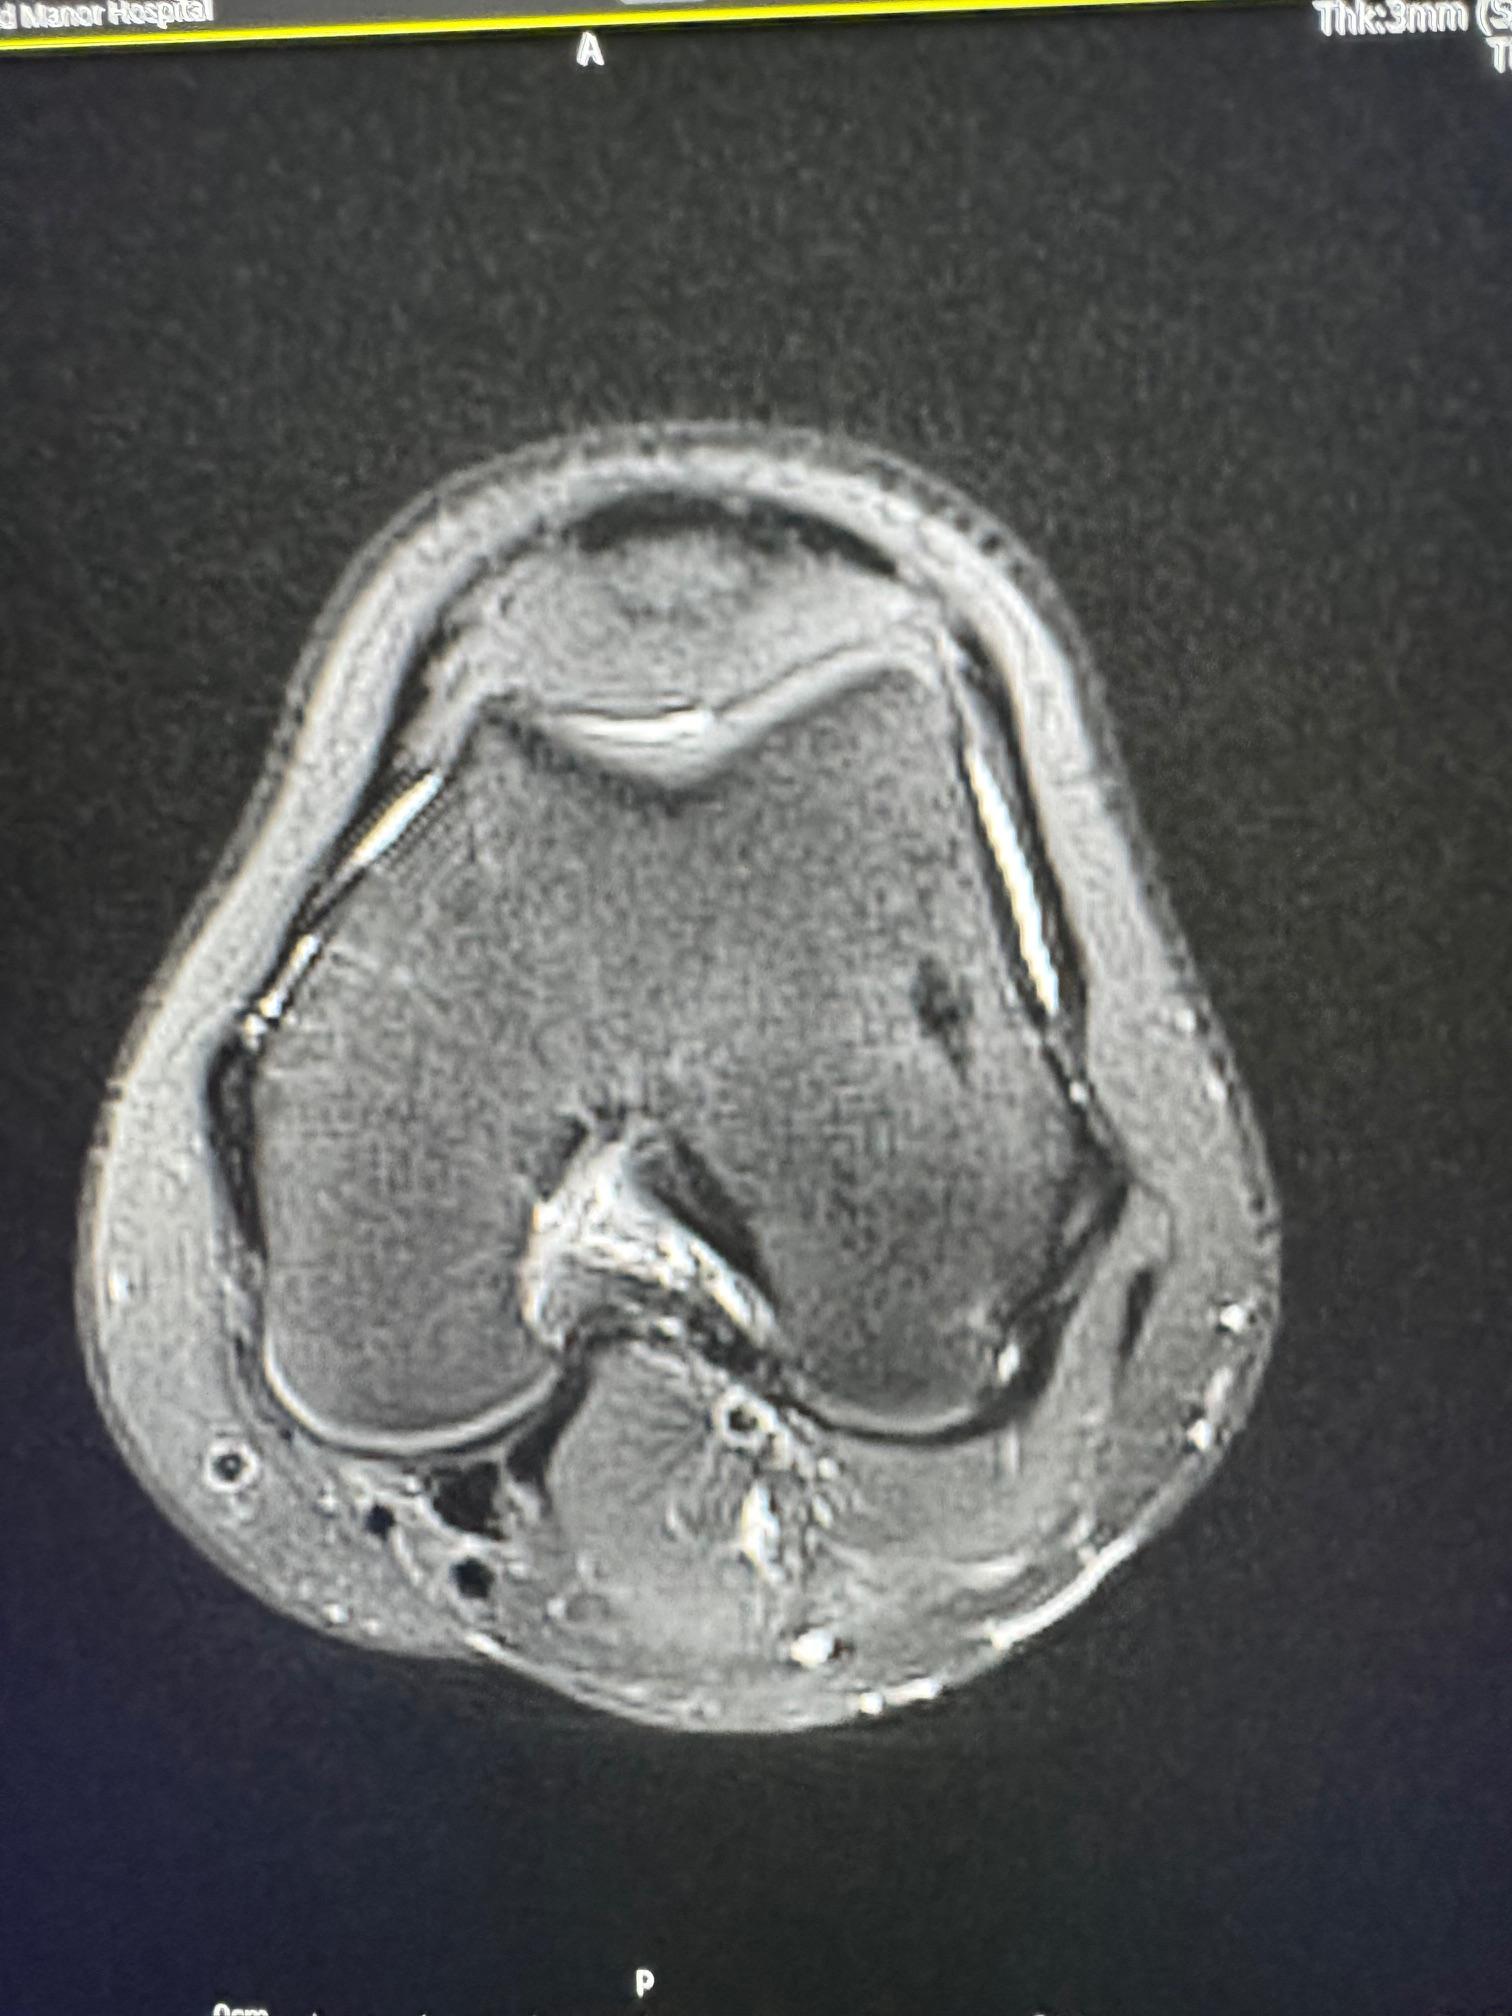

image5